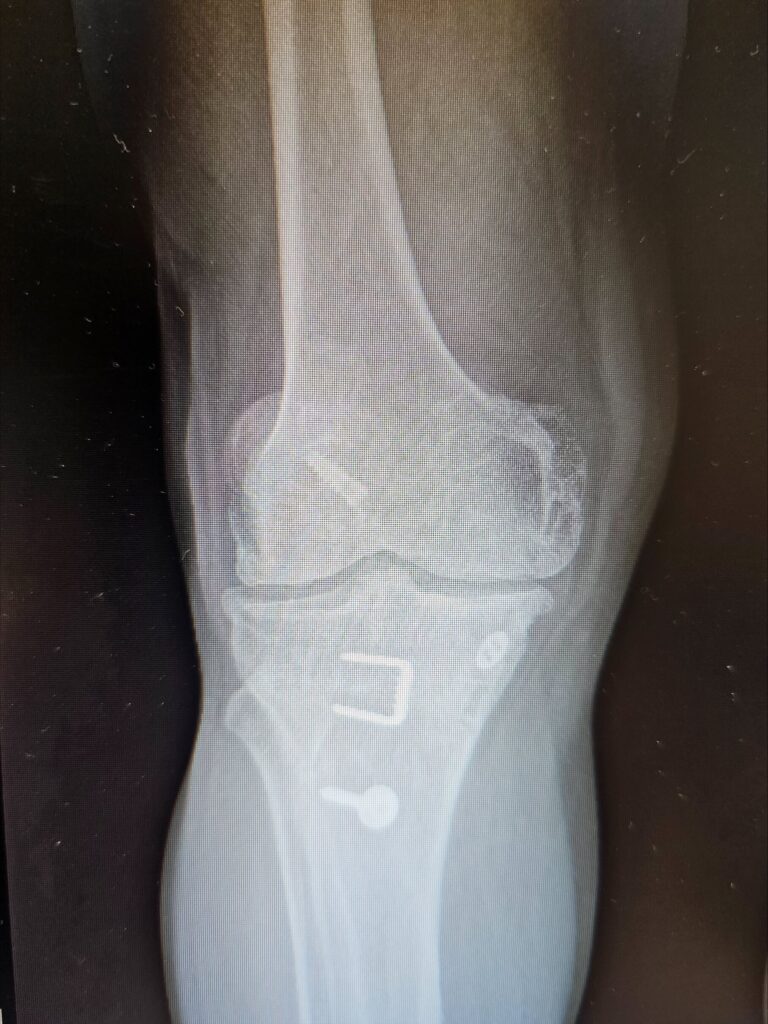

Last week marked a significant milestone in orthopedic surgery as Dr. Jared T. Lee, Medical Director and orthopedic surgeon at The Steadman Clinic in Aspen, Colorado, successfully performed the 5th ever customized press-fit total knee replacement in the United States — a monumental achievement that reflects his commitment to precision, innovation, and patient-centered care.

Traditional total knee replacements typically use standard implants fixed to bone with medical cement. In contrast, press-fit implants are designed to achieve stability through bone ingrowth — allowing the patient’s own bone to integrate with the implant surface over time rather than relying on cement fixation.

A customized press-fit knee goes even further: using advanced imaging (such as MRI or CT scans) taken before surgery, the implant is individually designed to match the exact anatomy of the patient’s knee joint. This tailored fit can improve alignment, preserve more bone, and maximize contact with the surrounding bone structure.

- Bone-preserving approach: Press-fit techniques can preserve more natural bone and may offer easier revision surgery if needed in the future.